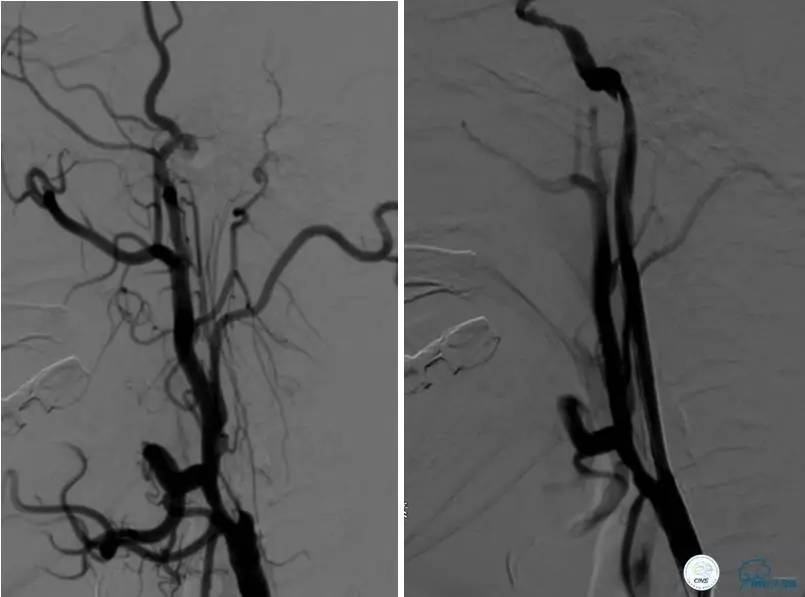

患者:49岁女性,脑梗死30天。

左侧颈内动脉末端闭塞,末端圆钝且有一定成角,开通难度较大,多次尝试导丝才成功穿过闭塞段。

开通效果很满意,术后症状明显恢复。